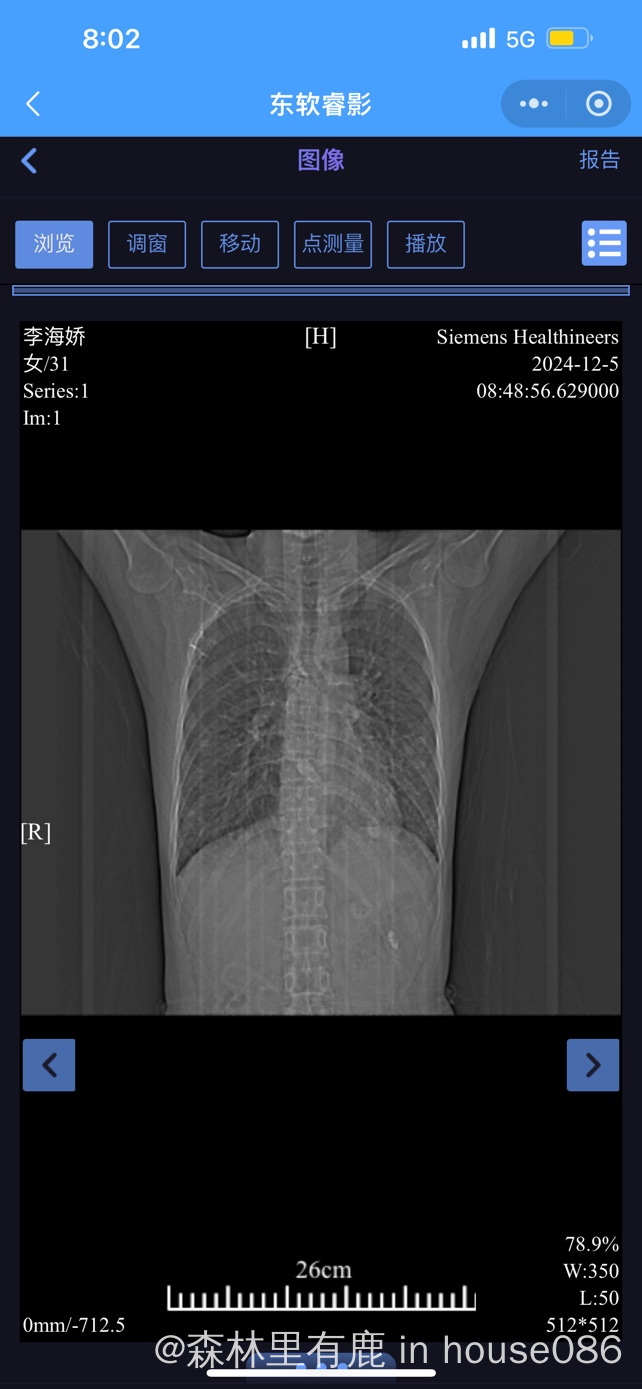

大家帮我看下胸部ct ,医生说右下肺叶很亚严重

现在也不知道是什么性质的肺炎,挂了几天抗生素,还每天会发烧几小时后才退烧